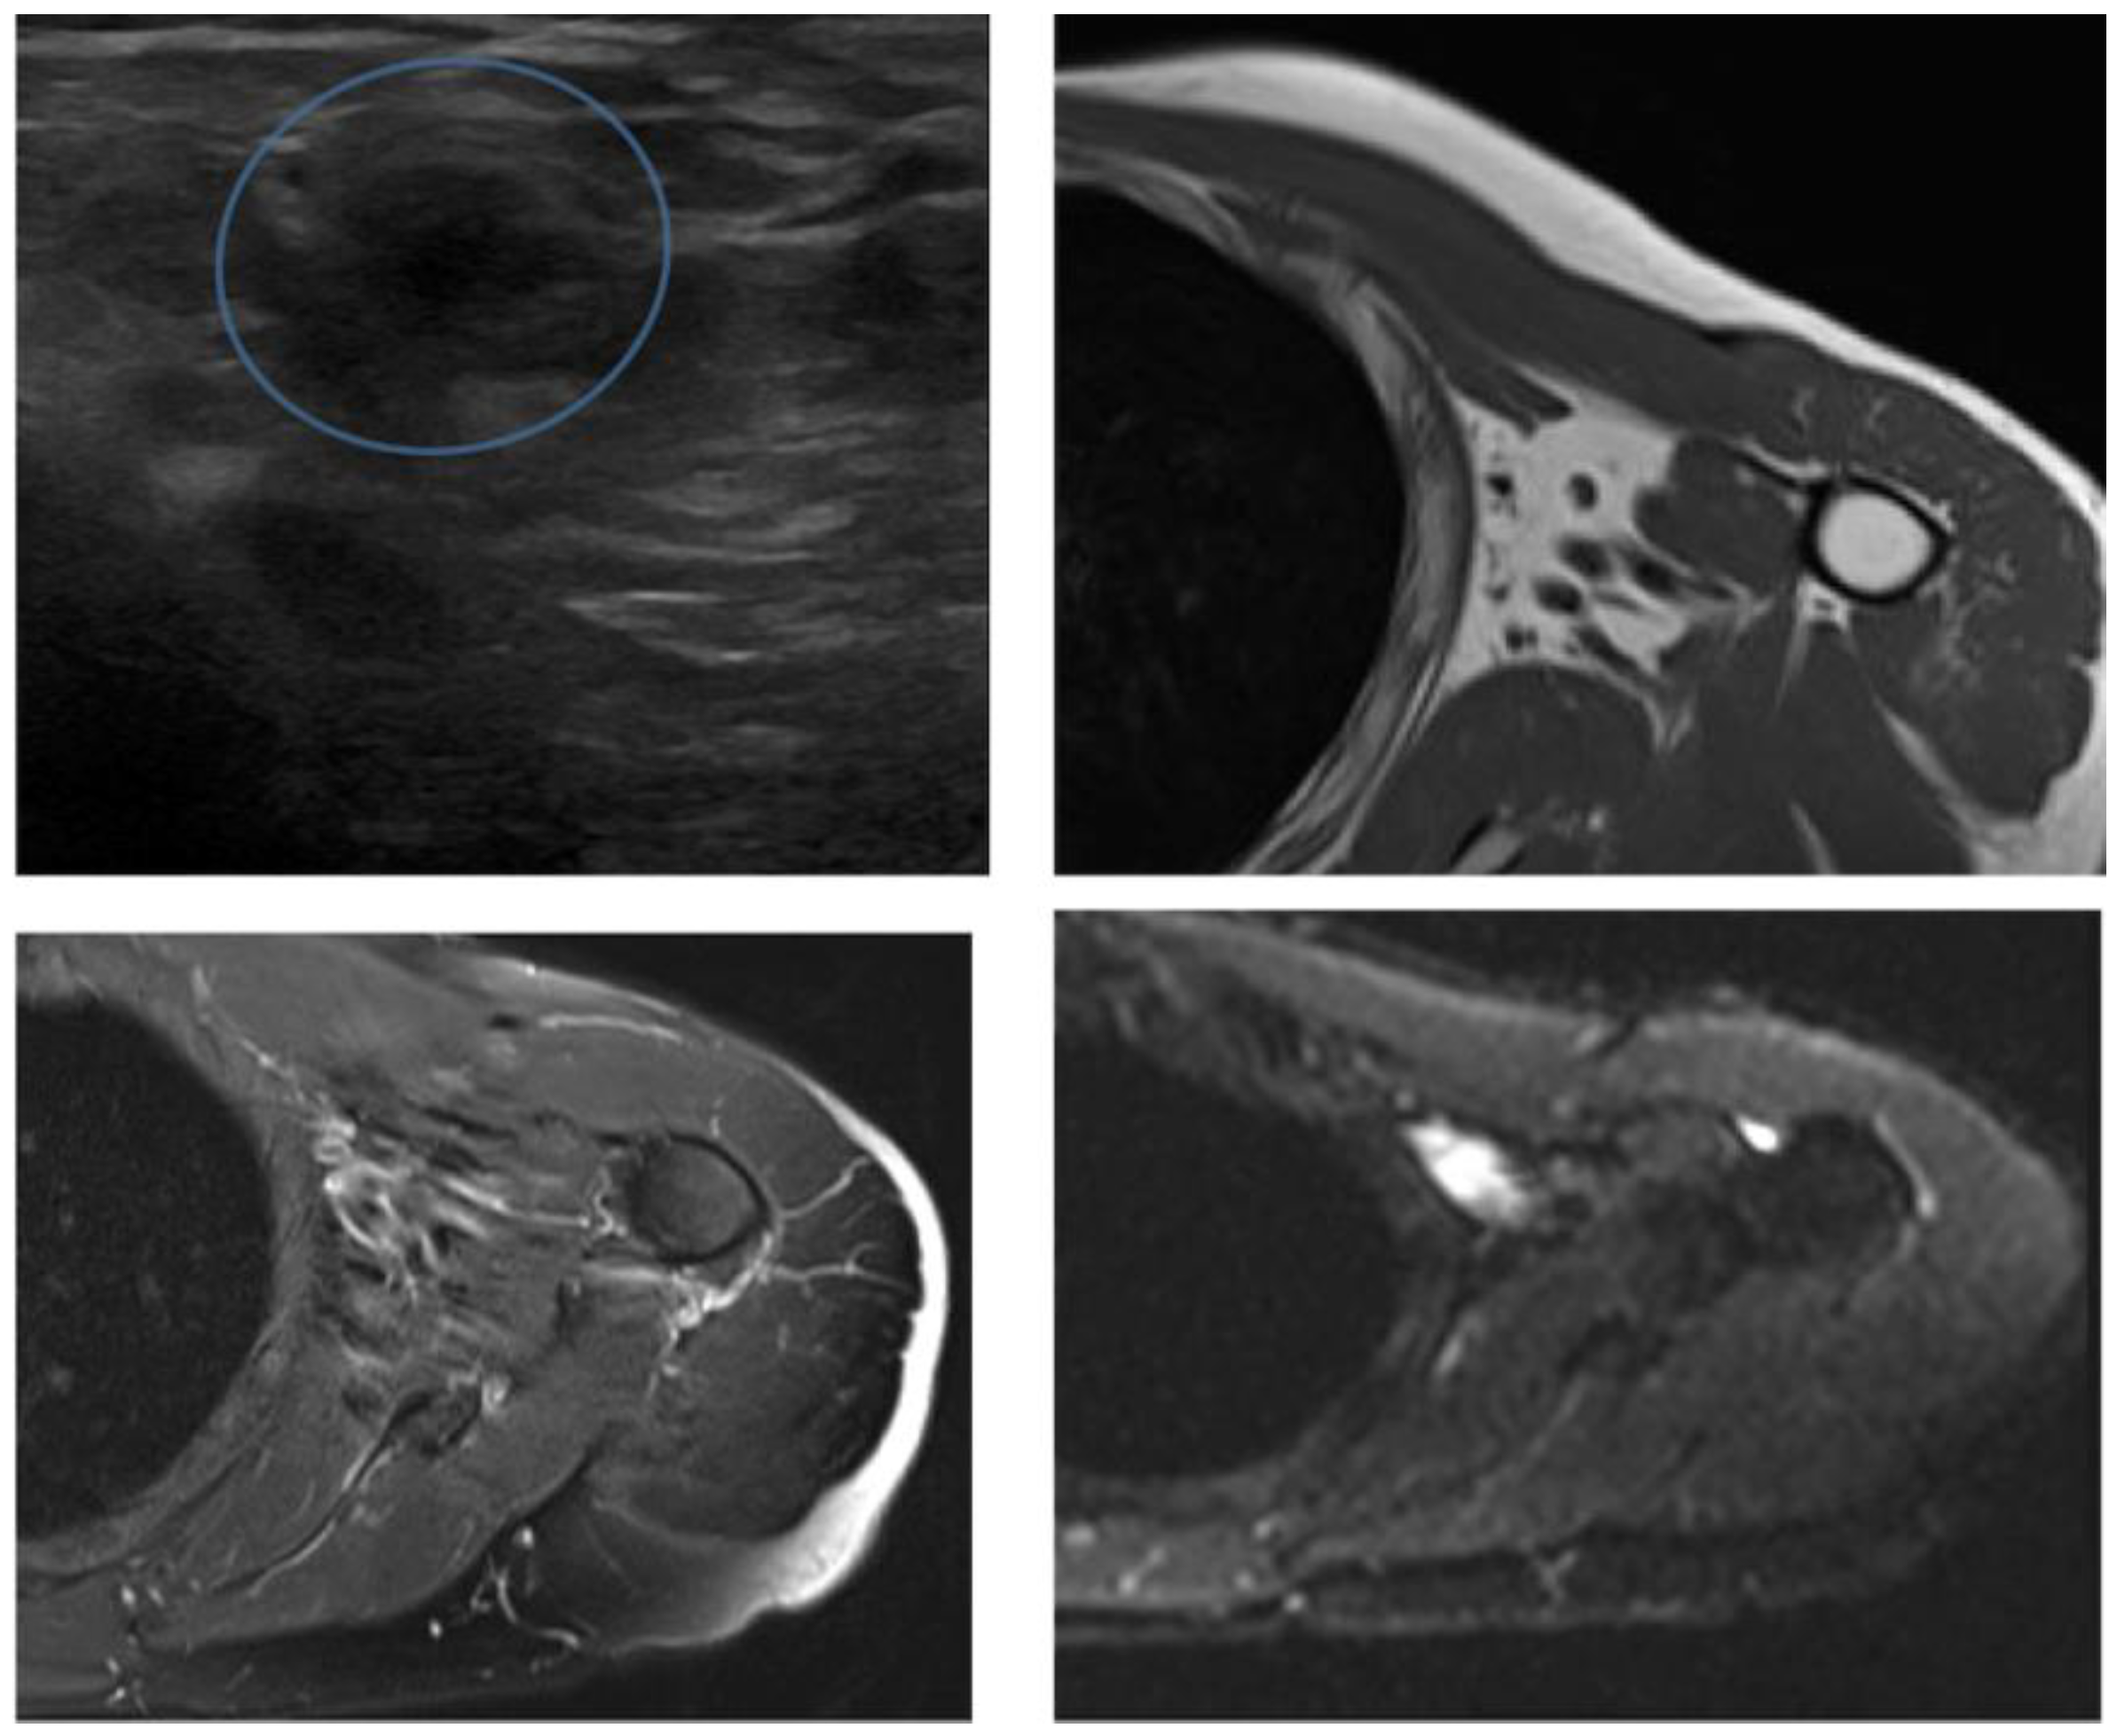

Magnetic Resonance Imaging or Ultrasound in Localized Intermediate- or High-Risk Soft Tissue Tumors of the Extremities (MUSTT): Final Results of a Prospective Comparative Trial

2.3. Ultrasound

2.4. Magnetic Resonance Imaging

- Tagliafico, A.S.; Bignotti, B.; Rossi, F.; Valdora, F.; Martinoli, C. Local recurrence of soft tissue sarcoma: A radiomic analysis. Radiol. Oncol. 2019, 53, 300–306. [Google Scholar] [CrossRef] [PubMed]

- Tagliafico, A.; Truini, M.; Spina, B.; Cambiaso, P.; Zaottini, F.; Bignotti, B.; Calabrese, M.; Derchi, L.E.; Martinoli, C. Follow-up of recurrences of limb soft tissue sarcomas in patients with localized disease: Performance of ultrasound. Eur. Radiol. 2015, 25, 2764–2770. [Google Scholar] [CrossRef] [PubMed]